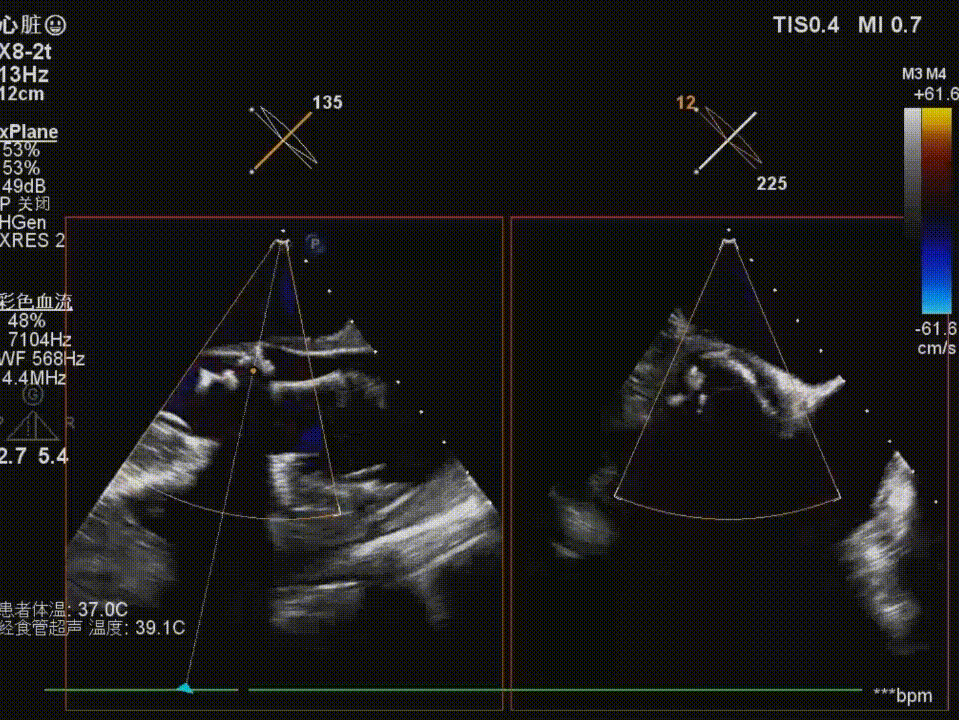

术前食道超声示:

瓣膜释放后造影及食道超声评估可见瓣膜释放形态欠佳,可见瓣周漏,并发现右冠开口血流缓慢,高度警惕右冠灌注障碍;

复查造影及食道超声示瓣膜位置,形态满意,瓣周漏较前明显好转,右冠血流恢复,无栓塞迹象;

术后食道超声示:

主动脉瓣血流速度及跨瓣压差较术前明显改善,未见明显反流,微量瓣周漏;右冠灌注良好。患者术后恢复顺利,未出现低灌注或心肌缺血相关并发症。